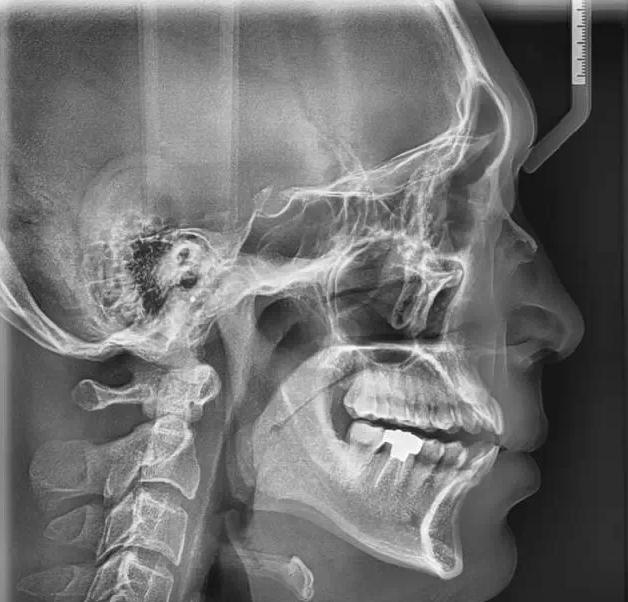

MSQJ2000-I口腔全景X射線機

產(chǎn)品簡介:

使用了50kHz高頻直流發(fā)生器,進(jìn)口齒科專用X射線管、手動式升降、電磁鎖定等,使其拍片時焦點小,圖像清晰,同時使X射線的輸出更加穩(wěn)定和準(zhǔn)確,從而減少了散射線對病人和操作人員不必要的輻射。并引進(jìn)日本先進(jìn)的scara投照平臺技術(shù)與工藝,使全景投照模式得以極大的拓展。豐富的投照程序選擇,為臨床診斷提供多種、實用的頜面影像信息。先進(jìn)的頜骨體層(全景)掃描技術(shù)方案使掃描聚焦與頜骨達(dá)到最佳彌合。直接成像影像還源性、清晰度均達(dá)到極高水平。

★  除了口腔全景影像,還能拍攝頭顱正、側(cè)位影像、四均分的顎關(guān)節(jié)共四種影像。

拍攝顎關(guān)節(jié)時,只要在取出牙托架和咬合桿后,本機功能即自動切換,即可對左右顎關(guān)節(jié)(開口、閉口)拍攝,具有均衡的放大率,可獲得一張四均分的顎關(guān)節(jié)X射線影像。

★  三條定位激光線確保了病人的正確定位。法蘭克福線正中矢狀線輔助校正病人頭部的角度,咬合校正光線確保正確的前部定位,在進(jìn)行簡單調(diào)整時,病人和醫(yī)生都可以在曲面鏡中看到正中矢狀平面。